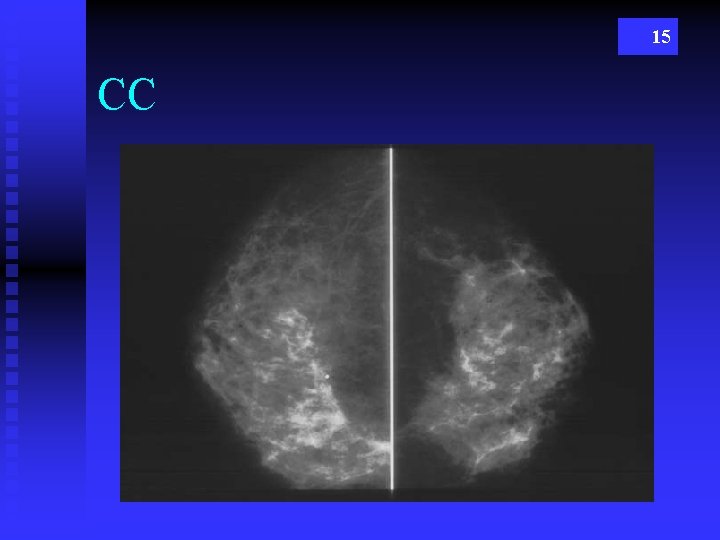

15 CC